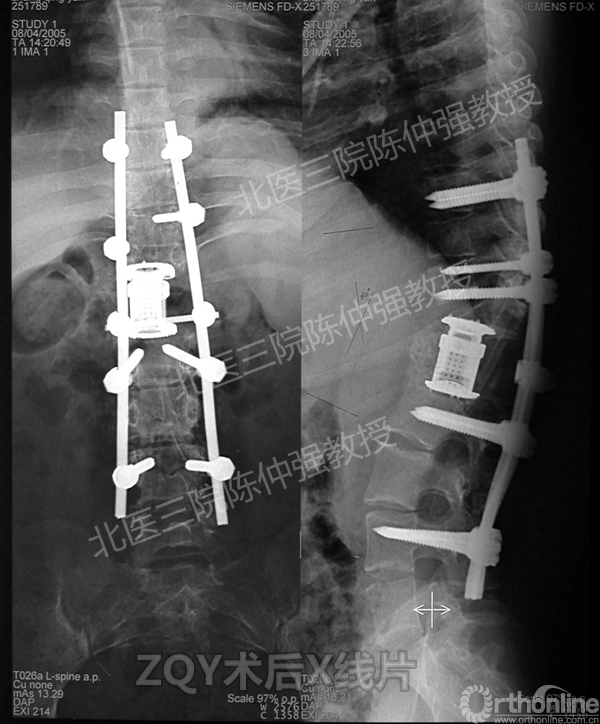

2005年,陈仲强教授在AOSpine年会上分享了一例胸腰椎陈旧结核性侧后凸畸形病例。资料如下:

ZQY术后

患者女性17岁,胸腰椎陈旧结核性侧后凸畸形,局部呈“麻花状”扭转,无神经功能受损表现。2005年,陈仲强教授带领团队实施后路+侧前方联合入路脊柱节段切除、双轴旋转矫形术。术后患者外观显著改善,神经功能正常。术后随访证实患者截骨矫形节段骨性融合良好,矫形效果持续良好。